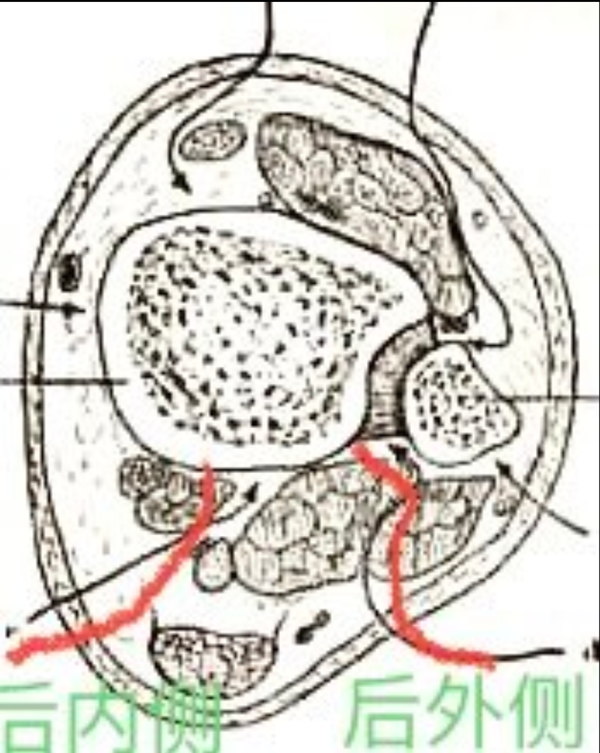

6、外踝后缘纵行切口。显露外踝,复位固定。然后钝性分离腓骨肌和踇长屈肌间隙,向前牵开腓骨肌并向后牵开屈拇长肌和跟腱显露胫骨远端后柱及后侧穹隆。

图6 显露后柱骨折的后外侧与后内侧切口